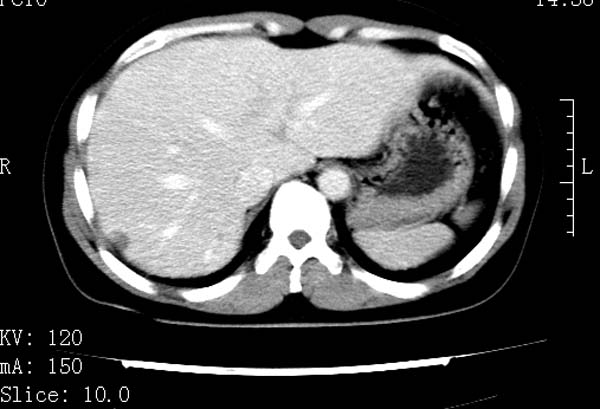

标题: CT22086:女44岁 肝右叶占位增强示巨大血管瘤,门脉期发现小 [打印本页]

标题: CT22086:女44岁 肝右叶占位增强示巨大血管瘤,门脉期发现小

支持肝右叶血管瘤诊断。 小病灶亦考虑血管瘤改变。温习一下:

肝海绵状血管瘤ct平扫常呈均匀低密度,与邻近血管密度相仿。在脂肪肝背景下可呈相对高密度。在增强扫描时,一般早期(动脉期)呈周边结节状或弧形强化,其密度与同层面的血管密度相仿,随着时间延迟向中央渐进性充填,注药后5~7分钟,逐渐扩大至全瘤强化,强化密度逐渐降至稍高于或等于正常肝脏。大的血管瘤往往中央有星形、大的低密度区,可以为纤维化或囊性变所致,纤维化成分可在延迟2 o分钟时完全充填,呈等密度,但囊变区则不会强化。不典型ct表现常见于≤3 cm的小血管瘤。小的血管瘤可以在动脉期即呈全部致密的均匀强化,不呈典型的周边结节状强化表现,但其密度往往较高,与主动脉相仿,在延迟期呈高或等密度。其他不典型的ct表现有:增强扫描强化不明显,呈点状较轻程度的强化,充填慢,可能与供血动脉较细和较大的血管间隙有关以及中央先强化等。

延迟扫描三个病灶都呈等密度改变。肝多发血管瘤,较典型。